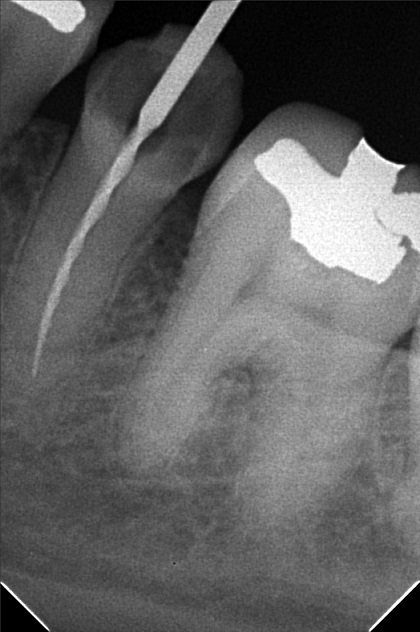

- 9/24/22 - Check up & Xray 10/01/22 - RCT 18mm , formacresol #35 10/08/22- RCT 17mm, campenol 10/15/22- 17.5MM PULP DEVITALIZER PAD done 11/05/22- Zirconia/LC 16 11/19/22- OP/Install Of Crowns